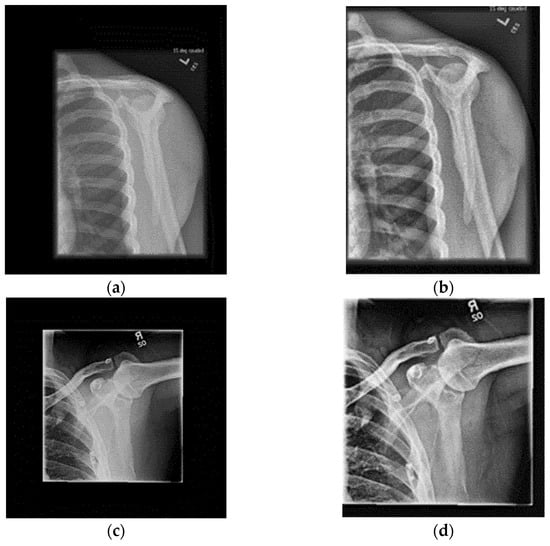

4.1. Dataset of Shoulder Bone X-ray Images

- Detection of the Corresponding Area: Most of the X-ray images in the used dataset were insufficient in terms of semantic information in relation to the image size. In order to eliminate such insufficiency, the images were first converted to gray-scale and then subjected to double thresholding and to an adaptive threshold value determined using Otsu’s thresholding value method. In the gray-scale images, the within-class variance value corresponding to all possible threshold values for the two color classes assumed as background and foreground was calculated. The threshold value that made this variance the smallest was the optimal threshold value. This method is known as Otsu’s thresholding value method [35]. Subsequently, the edge in the thresholded image was determined using edge detection methods. After this process, the original image was cropped based on the calculated values.

- CLAHE Transformation: In the next step, the contrast-limited adaptive histogram equalization (CLAHE) transformation in the OpenCV library was used. In the transformation used, the input image was divided into parts by the user, with each part containing a histogram within itself. The histogram of each part was then adjusted based on the histogram cropping limit entered by the user, and all parts were finally brought together to obtain a Clahe-transformed version of the input image [36,37]. New outputs were achieved by contrast equalization of the cropped images by the CLAHE method.

- Normalization and Standardization: In the last step, the images were normalized and standardized using the image-net values.